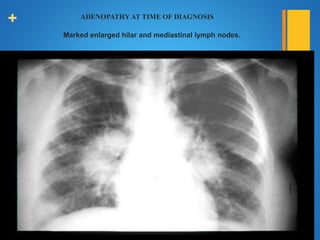

+ ADENOPATHY AT TIME OF DIAGNOSIS

Marked enlarged hilar and mediastinal lymph nodes.